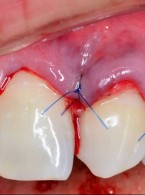

Jak postąpić w przypadku recesji dziąsłowych?

Zgłosiła się do mnie pacjentka z odsłoniętymi znacznie (ok. 4 mm) szyjkami kłów i zębów przedtrzonowych szczęki od strony przedsionkowej. Powierzchnia korzeni nie jest zmieniona, ale pacjentka skarży się na wrażliwość odsłoniętych powierzchni i ich nieestetyczny wygląd. Czy można je w jakiś sposób pokryć i jakie jest rokowanie w takich przypadkach?